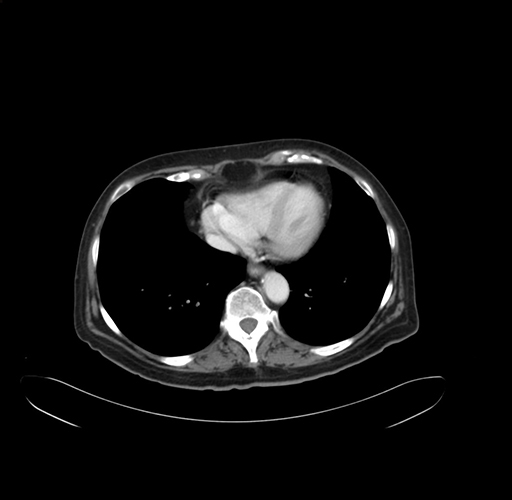

Pre-Chemo: Axial Venous